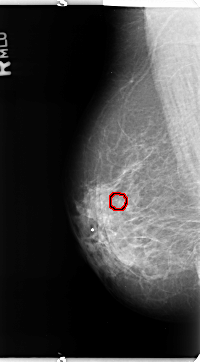

FILE: B_3364_1.RIGHT_CC.OVERLAY

TOTAL_ABNORMALITIES 1

ABNORMALITY 1

LESION_TYPE CALCIFICATION TYPE PLEOMORPHIC DISTRIBUTION CLUSTERED

ASSESSMENT 4

SUBTLETY 3

PATHOLOGY BENIGN

TOTAL_OUTLINES 1

BOUNDARY